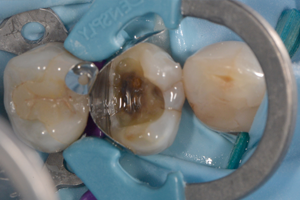

Composiet wordt wereldwijd beschouwd als eerste keuze materiaal voor directe restauraties in de posterieure regio. De levensduur van de posterieure composietrestauratie is gunstig. Verschillende reviews noteren een jaarlijks faalpercentage van 1-3%. Een correct uitgevoerde klinische procedure speelt een kritische rol m.b.t de levensduur van de posterieure composietrestauratie.

In deze lezing wordt dieper ingegaan op de verschillende stappen bij het plaatsen van de enkelvoudige posterieure composietrestauratie: de keuze van het composiet en adhesief systeem, de caviteitspreparatie, afzondering, het matrixsysteem, laagjes techniek versus bulk fill, vormgeving, occlusie en afwerking. Zowel de meer beperkte als uitgebreide posterieure composietrestauratie met knobbelopbouw komen aan bod. Tenslotte wordt belicht dat regelmatig onderhoud en lokaal herstel van de defecte posterieure composietrestauratie de levensduur zal verlengen.